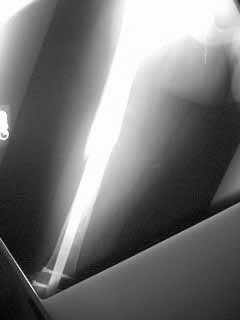

Pt is 27 yo construction worker now 5 months post fx. He has tenderness localized over distal locking screw heads. CT confirms bridging bone posteriorly. How much healing is necessary? Suggestions for further management are appreciated.

2. Consider bone grafting the gap in the distal femur where the spiral looks displaced.

I can't dynamise the nail by removing the distal locking because of its spiral fracture line. Dynamise will be unstable to the fracture. And the case has tenderness in the distal locking region . It may be refracturearound the distal hole . I don't want to use bone grafting because it will disturb the soft tissue and may not be good to fracture healing.

From what you say, I'd be slow to do anything fast - certainly not remove screws or bone graft yet - 5 months is not very long since injury, especially if he's still healing. I'd review serial, better quality x-rays. Not just AP & Lat, but both obliques as well. I'm assuming he's fully weightbearing a, has good motion and is progressing satisfactorily with rehab, and that his "locking screw head pain" is tolerable. If he fails to progress, or has significantly limited activity, then perhaps suspect nonunion or structural insufficiency. Does the anterior bone prominence bother him? Knee motion ok? Isn't there some new bone in the anterior gap?

I did get CT which confirms union along the posterior cortex.

He has excellent knee ROM with no ant thigh pain or tenderness. Minimal ant new bone.